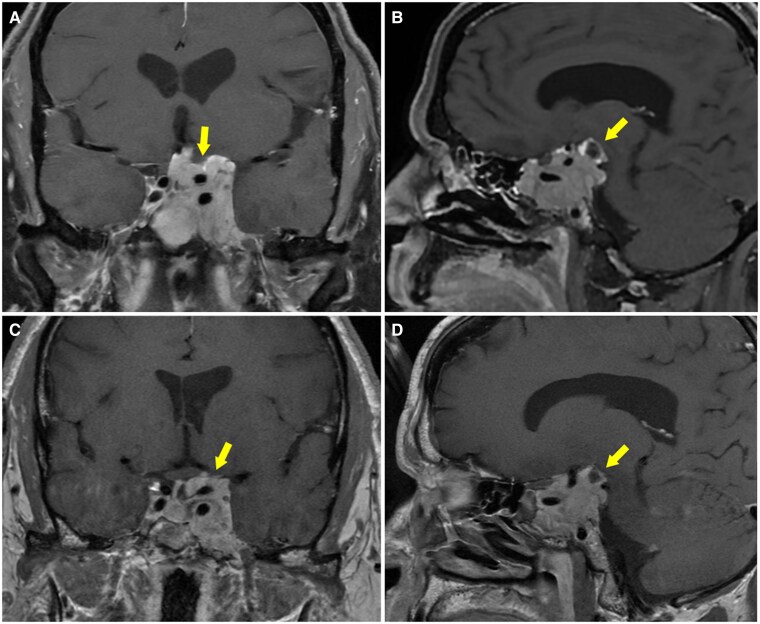

Prolactin-secreting pituitary adenomas are typically treated with dopamine agonists to inhibit prolactin secretion and reduce tumor size. Dopamine-secreting paragangliomas are rare neuroendocrine tumors of sympathetic and parasympathetic paraganglia and often do not provoke symptoms of catecholamine excess. Although overlapping genetic drivers have been described for paragangliomas and pituitary adenomas, biochemical crosstalk between coexisting tumors is underexplored. We describe the case of a 52-year-old male individual who presented with cerebrospinal fluid (CSF) rhinorrhea and was found to have an invasive, 4.2-cm pituitary mass with modestly elevated prolactin (130.9 ng/mL [130.9 µg/L], reference range [RR] 2-18 ng/mL [2-18 µg/L]). Additional imaging discovered a mediastinal mass suspicious for a thoracic paraganglioma. Biochemical screening demonstrated marked elevation of plasma and urinary dopamine. Following paraganglioma resection, dopamine levels normalized, but prolactin rose significantly (877.8 ng/mL [877.8 µg/L]), suggesting an endogenous dopamine agonist-like effect from the paraganglioma to suppress pituitary prolactin hypersecretion. Pituitary pathology was notable for a PIT1 (pituitary transcription factor-1)-lineage pituitary adenoma with absent immunohistochemical staining for prolactin. Genetic testing found a previously unreported germline SDHC variant of uncertain significance. In this case, we report a novel biologic signaling mechanism between 2 rare primary endocrine tumors and highlight challenges in their diagnosis and management.